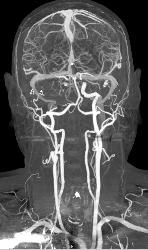

CTA With Dual Energy and Bone Removal